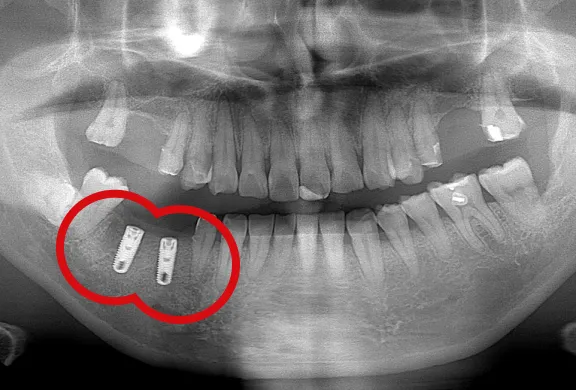

分割抜歯について

また当院では分割抜歯も行っております。歯の根っこが悪くなり抜歯しなくてはならないケースでも、状態によっては悪くなっている部分だけを抜歯して、できるだけ歯自体を残せるように努めています。

下顎のインプラント(4本)

下顎のインプラント(2本)